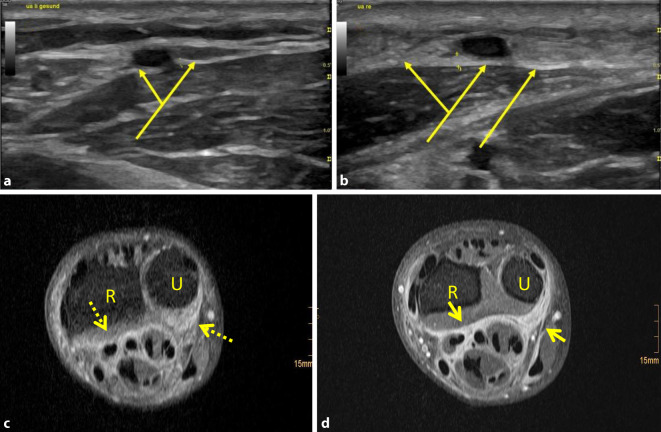

Eosinophilic fasciitis (EF, also known as Shulman syndrome) is an uncommon connective tissue disease characterized by inflammatory thickening of the fasciae as well as swelling and hardening of the skin. It mostly affects the lower extremities. Swollen and indurated skin, together with the groove sign, are typical clinical signs. So far, biopsy evidence of inflammation and thickening of the fascia has been the gold standard for diagnosis. Magnetic resonance imaging (MRI) is mentioned in the literature as an alternative method for confirming the diagnosis. We present a case of asymmetric EF in a 54-year-old German male. He came with painful induration of the right forearm, with a characteristic groove sign and limitation of motion of the right hand. The blood count revealed eosinophilia with 0.57 G/l or 9.6% (normal: 0.05-0.5 G/l and 0.5-5.5%), ANA and ENA were negative. The diagnosis was confirmed histologically and we were able to detect a thickened fascia in MRI and ultrasound imaging. The EF also appeared in the left lateral malleolus during the course of the illness. Treatment was carried out with prednisolone and methotrexate.